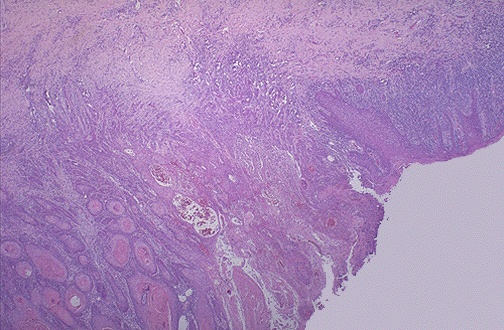

| This is the microscopic appearance of neoplasia, or uncontrolled new growth. Here, the neoplasm is infiltrating into the underlying cervical stroma. Of course, there can be carcinoma in situ in which a full-fledged neoplasm is present, but has not yet invaded. Over time, neoplasms may acquire characteristics that make them able to invade tissues, and this distinguishes them as malignant. |